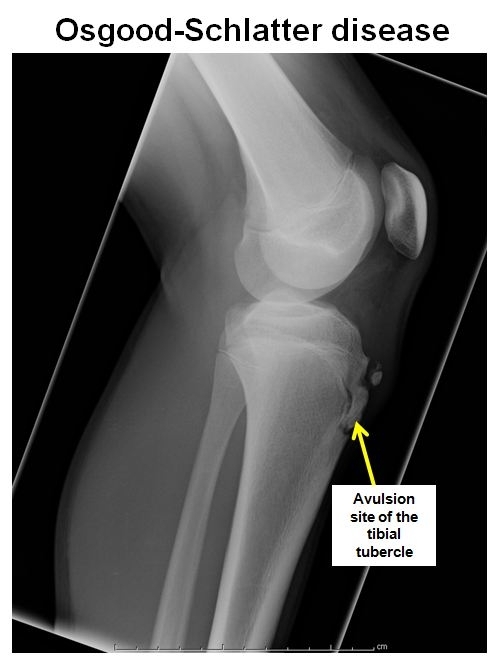

.,

X-ray of the knee typically shows avulsion of the apophysis of the tibial tubercle.